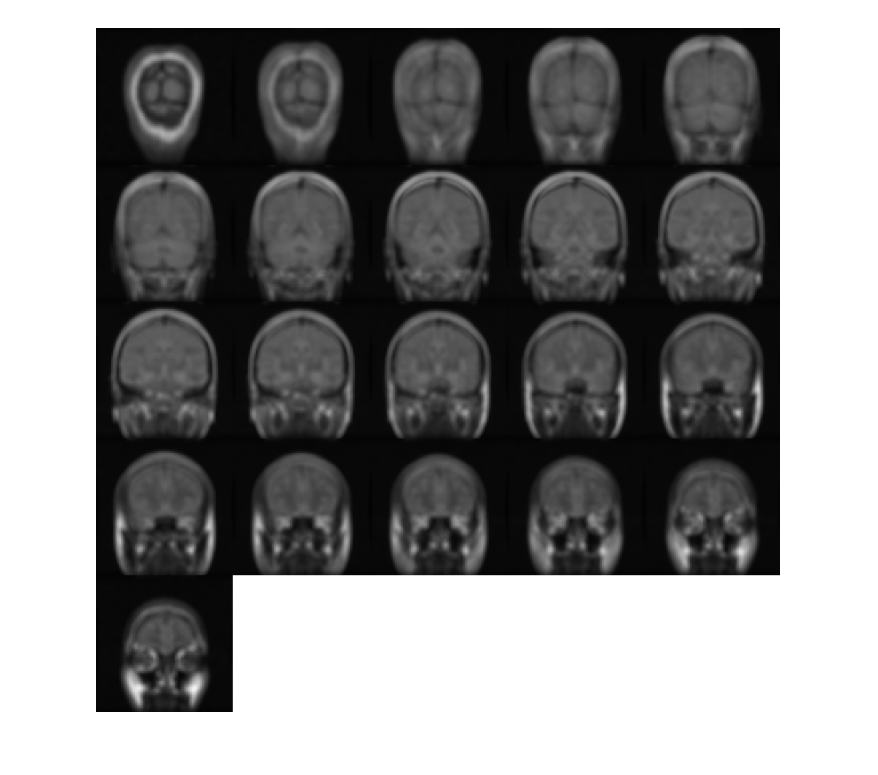

Создайте 3-D эллипсоидальный фильтр. Задайте длину полуоси 7 пикселей в y (строки) и x (столбцы) направления и длина полуоси 3 пикселей в z (плоскости) направление.

H = fspecial3('ellipsoid',[7 7 3]);

Сглаживайте объем с фильтром.

volSmooth = imfilter(mristack,H,'replicate');

Отобразите плоскости сглаживавшего объема.

montage(volSmooth,'BackgroundColor','w')

Figure contains an axes. The axes contains an object of type image.